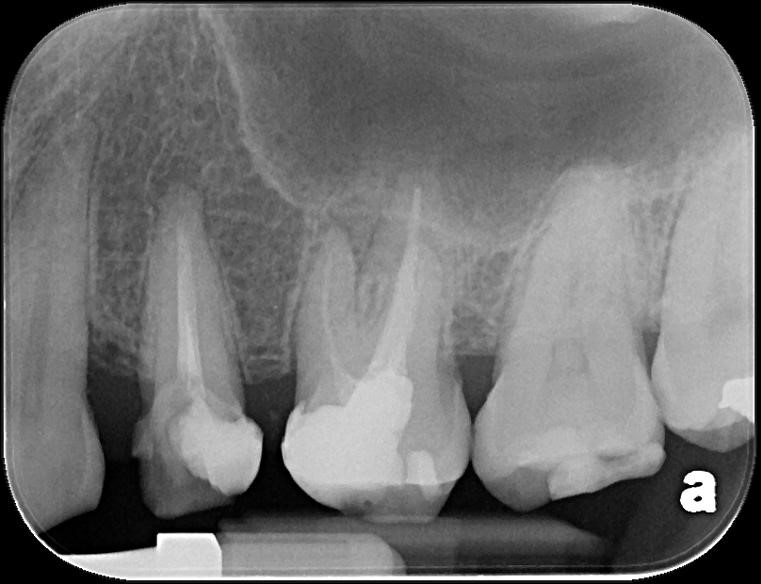

治療前,第二小臼齒根尖病變

顯微根管重治療